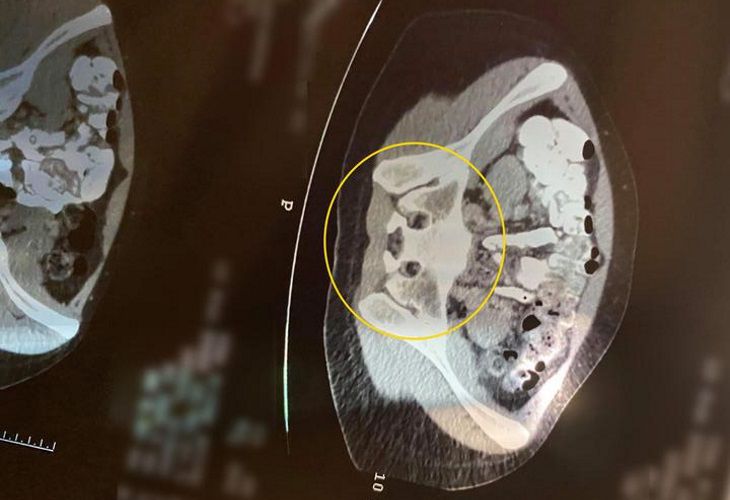

Однако на одном из снимков Александра заметила необычный феномен — на скане была «изображена» мордочка ее четвероногого любимца – спаниеля Джроджа.

Причем обнаружила она это в месте, где идет поперечное сечение таза и крестца — кости, которые находятся у основания позвоночника.

По мнению девушки, странная комбинация костей очень сильно напоминает ее собаку.